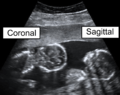

Coronal plane

A coronal plane (also known as the frontal plane) is any vertical plane that divides the body into ventral and dorsal (belly and back) sections.

The coronal plane is an example of a longitudinal plane, because it is perpendicular to the transverse plane. For a human, the mid-coronal plane would transect a standing body into two halves (front and back, or anterior and posterior) in an imaginary line that cuts through both shoulders.